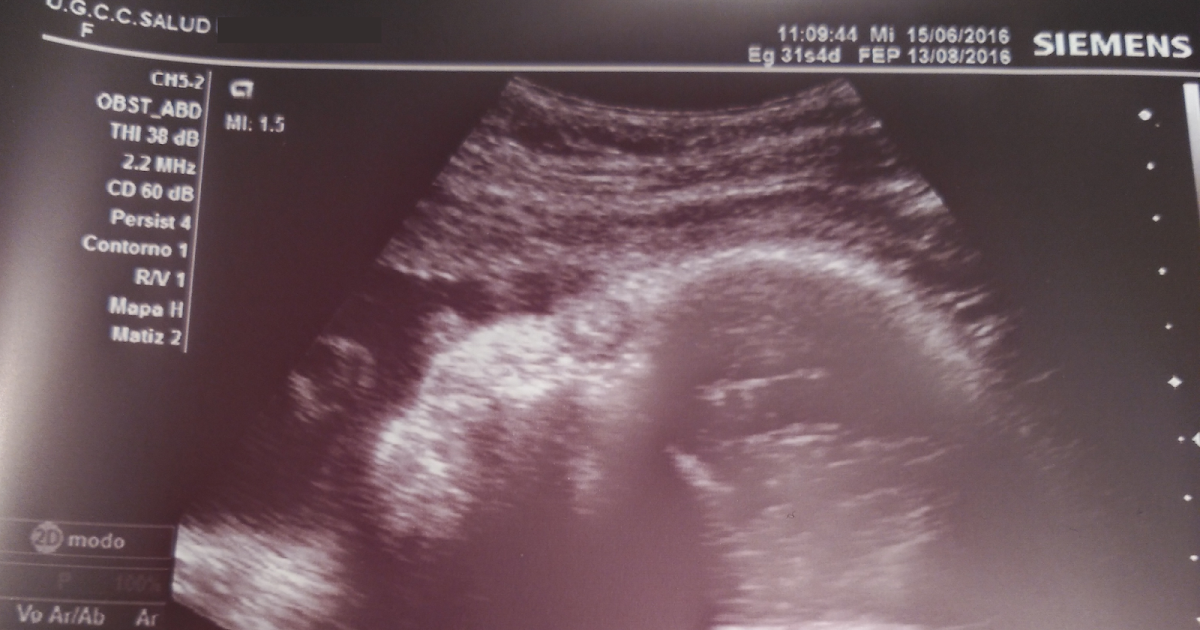

WebEcografía de 32 semanas, preocupada????: Hola mamitas, hoy tuve mi ecografía de las 32 semanas, mi bebé está como de 34 semanas y pesa 2.392 gramos, pero tiene el cordón enredado en el cuello de resto está todo bien, pero eso me dejó muy preocupada. WebAdemás, permite valorar el bienestar fetal en tercer trimestre. En las gestaciones que evolucionan bien se suele hacer entre semanas 32 y 34 de embarazo; en las. Web"no te preocupes" hola,te cuento mi esperiencia.Tengo un bebe de dos meses que peso al nacer 3.200kg y midio 48cm,y en la eco de las 32 semanas que me.

Ecografia 32 Semanas Y Muy Preocupada, MI ECOGRAFIA NO COINCIDE CON MIS SEMANAS DE GESTACIÓN, POR GINECOLOGA DIANA ALVAREZ, 16.89 MB, 12:18, 250,932, Ginecologa Diana Alvarez, 2019-06-04T01:33:00.000000Z, 3, Semana 32 de Embarazo (Síntomas, Movimientos, Panza y Ecografía), embarazosybebes.info, 768 x 556, jpeg, , 20, ecografia-32-semanas-y-muy-preocupada, New Topics

Semana 32 de Embarazo (Síntomas, Movimientos, Panza y Ecografía) tendencias